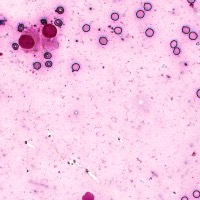

Medical Diagnosis: The "4class" model can be employed by pathologists to accurately identify and quantify the different cell types in blood and tissue samples, assisting in the diagnosis of various blood disorders and diseases, including anemia, leukemia, and infections.

Research and Drug Development: Researchers can use the "4class" model to analyze cellular response to experimental treatments, providing essential data for drug discovery, evaluating the efficacy of novel compounds, and understanding cell behavior under various conditions.

Education and Training: The "4class" computer vision model can serve as an educational tool for medical students and professionals, facilitating their understanding of different cell types, their characteristics, and functions, while promoting accurate identification in laboratory settings.

Automated Screening: Integration of the "4class" computer vision model into medical laboratory equipment can automate the process of cell classification during screenings or biopsies. This can help save time and reduce the risk of human errors during the evaluation of samples.

Telemedicine and Remote Analysis: The "4class" model can support telemedicine platforms, making it possible for healthcare professionals to remotely access and evaluate blood and tissue samples. This would be particularly useful in underserved areas, where access to pathologists might be limited.